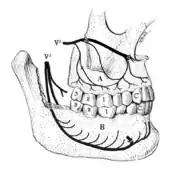

Pericoronitis is inflammation of the soft tissues surrounding the crown of a partially erupted tooth.[25] The lower wisdom tooth is the last tooth to erupt into the mouth, and is, therefore, more frequently impacted, or stuck, against the other teeth. This leaves the tooth partially erupted into the mouth, and there frequently is a flap of gum (an operculum), overlying the tooth. Bacteria and food debris accumulate beneath the operculum, which is an area that is difficult to keep clean because it is hidden and far back in the mouth. The opposing upper wisdom tooth also tends to have sharp cusps and over-erupt because it has no opposing tooth to bite into, and instead traumatizes the operculum further. Periodontitis and dental caries may develop on either the third or second molars, and chronic inflammation develops in the soft tissues. Chronic pericoronitis may not cause any pain, but an acute pericoronitis episode is often associated with pericoronal abscess formation. Typical signs and symptoms of a pericoronal abscess include severe, throbbing pain, which may radiate to adjacent areas in the head and neck,[21][26]:122 redness, swelling and tenderness of the gum over the tooth.[27]:220–222 There may be trismus (difficulty opening the mouth),[27]:220–222 facial swelling, and rubor (flushing) of the cheek that overlies the angle of the jaw.[21][26]:122 Persons typically develop pericoronitis in their late teens and early 20s,[28]:6 as this is the age that the wisdom teeth are erupting. Treatment for acute conditions includes cleaning the area under the operculum with an antiseptic solution, painkillers, and antibiotics if indicated. After the acute episode has been controlled, the definitive treatment is usually by tooth extraction or, less commonly, the soft tissue is removed (operculectomy). If the tooth is kept, good oral hygiene is required to keep the area free of debris to prevent recurrence of the infection.[21]:440–441